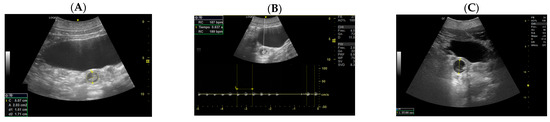

- Day 219 ± 3 days: It is also possible to recognize the eye as an anechoic cavitary structure (Figure 6). During the last month of pregnancy, it is possible to easily identify most of the abdominal organs such as the liver, spleen, intestine, and kidneys (Figure 7). In addition, the genitalia are visible and it could be possible to establish the sex of the fetus: in males, it is possible to identify the penis bone, which is obviously absent in females, but its visualization depends strongly on fetal position.